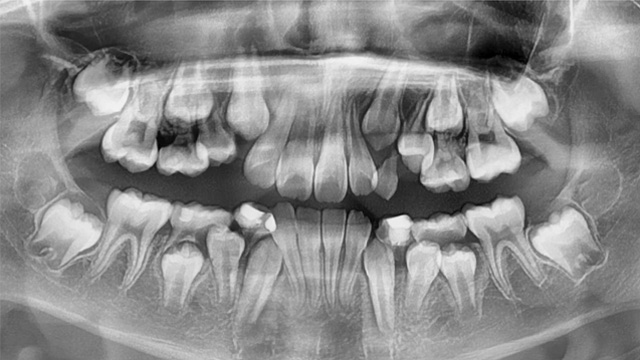

晴晴的口腔全景片(牙齿拥挤、乳牙滞留)